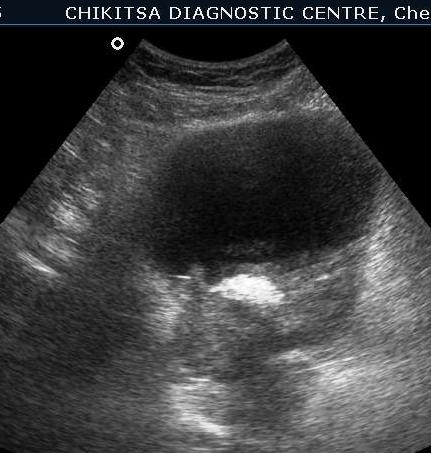

March 2012 :

5 5 cm x 5 cm size ill-defined heterogeneous area in the posterior wall of the urinary bladder which is thickened and measures upto 0.6 cm in thickness. Large solid calcific areas are noted in the thicknened portion of the wall urinary bladder. Suggestive of schistosomiasis of the urinary bladder (possibly with malignant change).

Left kidney shows hydronephrosis.